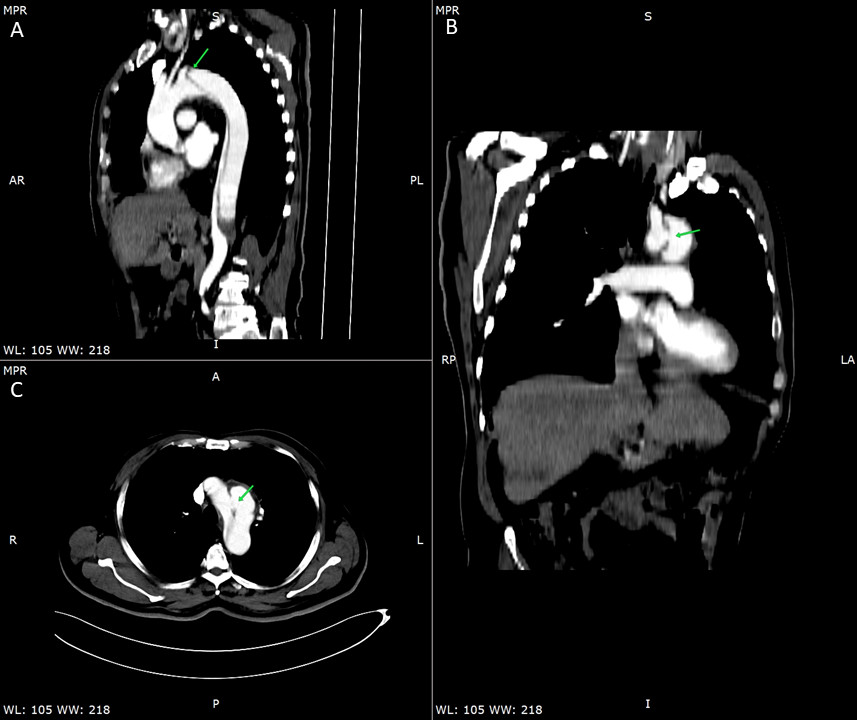

入院后查肌酸激酶-MB、肌红蛋白和N端脑钠肽前体结果均为阴性。肌酐和甲状腺功能结果正常。超敏肌钙蛋白T(hs-TNT)轻度升高(19.7 ng/L,正常范围:0~14 ng/L),D-二聚体(D-D)为2.21 mg/L(正常范围:0~0.5 mg/L)。感染四项阴性。经胸超声心动图除外心内膜炎,诊断考虑肺栓塞或其他潜在病因,行胸腹部增强CT扫描,结果显示Stanford B型主动脉夹层,近端左锁骨下动脉附近1.6 cm内膜破裂,延伸至T12和L1椎体水平;其中假腔由主动脉弓延伸至腹主动脉,伴腔内血栓形成(图 1)。

| A、B、C为Stanford B型主动脉夹层,假腔由近端左锁骨下动脉附近1.6 cm延伸至腹主动脉T12-L1椎体水平 图 1 起病19 d时胸腹增强CT |